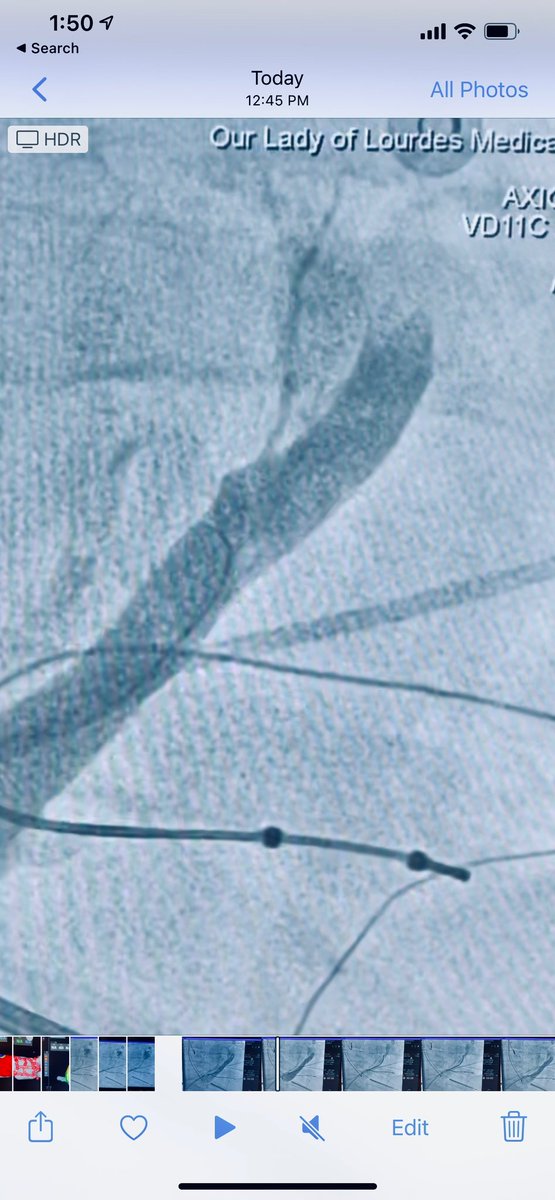

Difficult mitral isthmus line after mitral flutter induced post atrial fibrillation ablation. Intermittent block with multiple endocardial burns. Bidirectional block after VOM injection with dramatic increase in endocardial scar on right @VirtuaHealth @VirtuaHRS @AatishGarg_EP

Delighted to start the Vein of Marshall alcohol ablation program at @VirtuaHealth with @VirtuaHRS Grateful to @jaykoneru and @KennethEllenbo1 for their guidance along with @MiguelVldrbno and @EPbordeaux for their groundbreaking research articles.